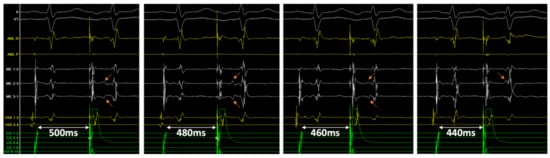

3.5. Double Potentials